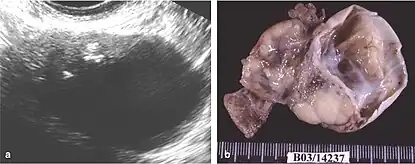

Mature cystic teratoma

Mature cystic teratoma (MCT), affecting women in 10–20% of cases during their lifetime, is characterized by benign mature cystic teratomas—an intriguing subject in gynecological pathology.[8][3] These non-cancerous tumors, originating from at least two embryonic germ cell layers, exhibit a complex interplay of developmental pathways, stemming from singular germ cells or the complexities of meiosis I and II failure.[9][10] Internally lined with squamous epithelium and externally connected to the ovarian stroma, mature cystic teratomas contain diverse fluids such as sebaceous, serous, or mucinous.

Although the majority of MCT cases are non-malignant, approximately 0.17-2% may undergo malignant transformation, with squamous cell carcinoma being the most prevalent, constituting 80% of such transformations.[11] The clinical presentation of oSCC development within MCT lacks specificity, often resulting in the inadvertent discovery of early-stage tumors during routine examinations or postoperative assessments. In advanced cases, patients may exhibit palpable masses, abdominal swelling, and pain, potentially leading to acute abdominal complications due to tumor involvement.[10][12][4]